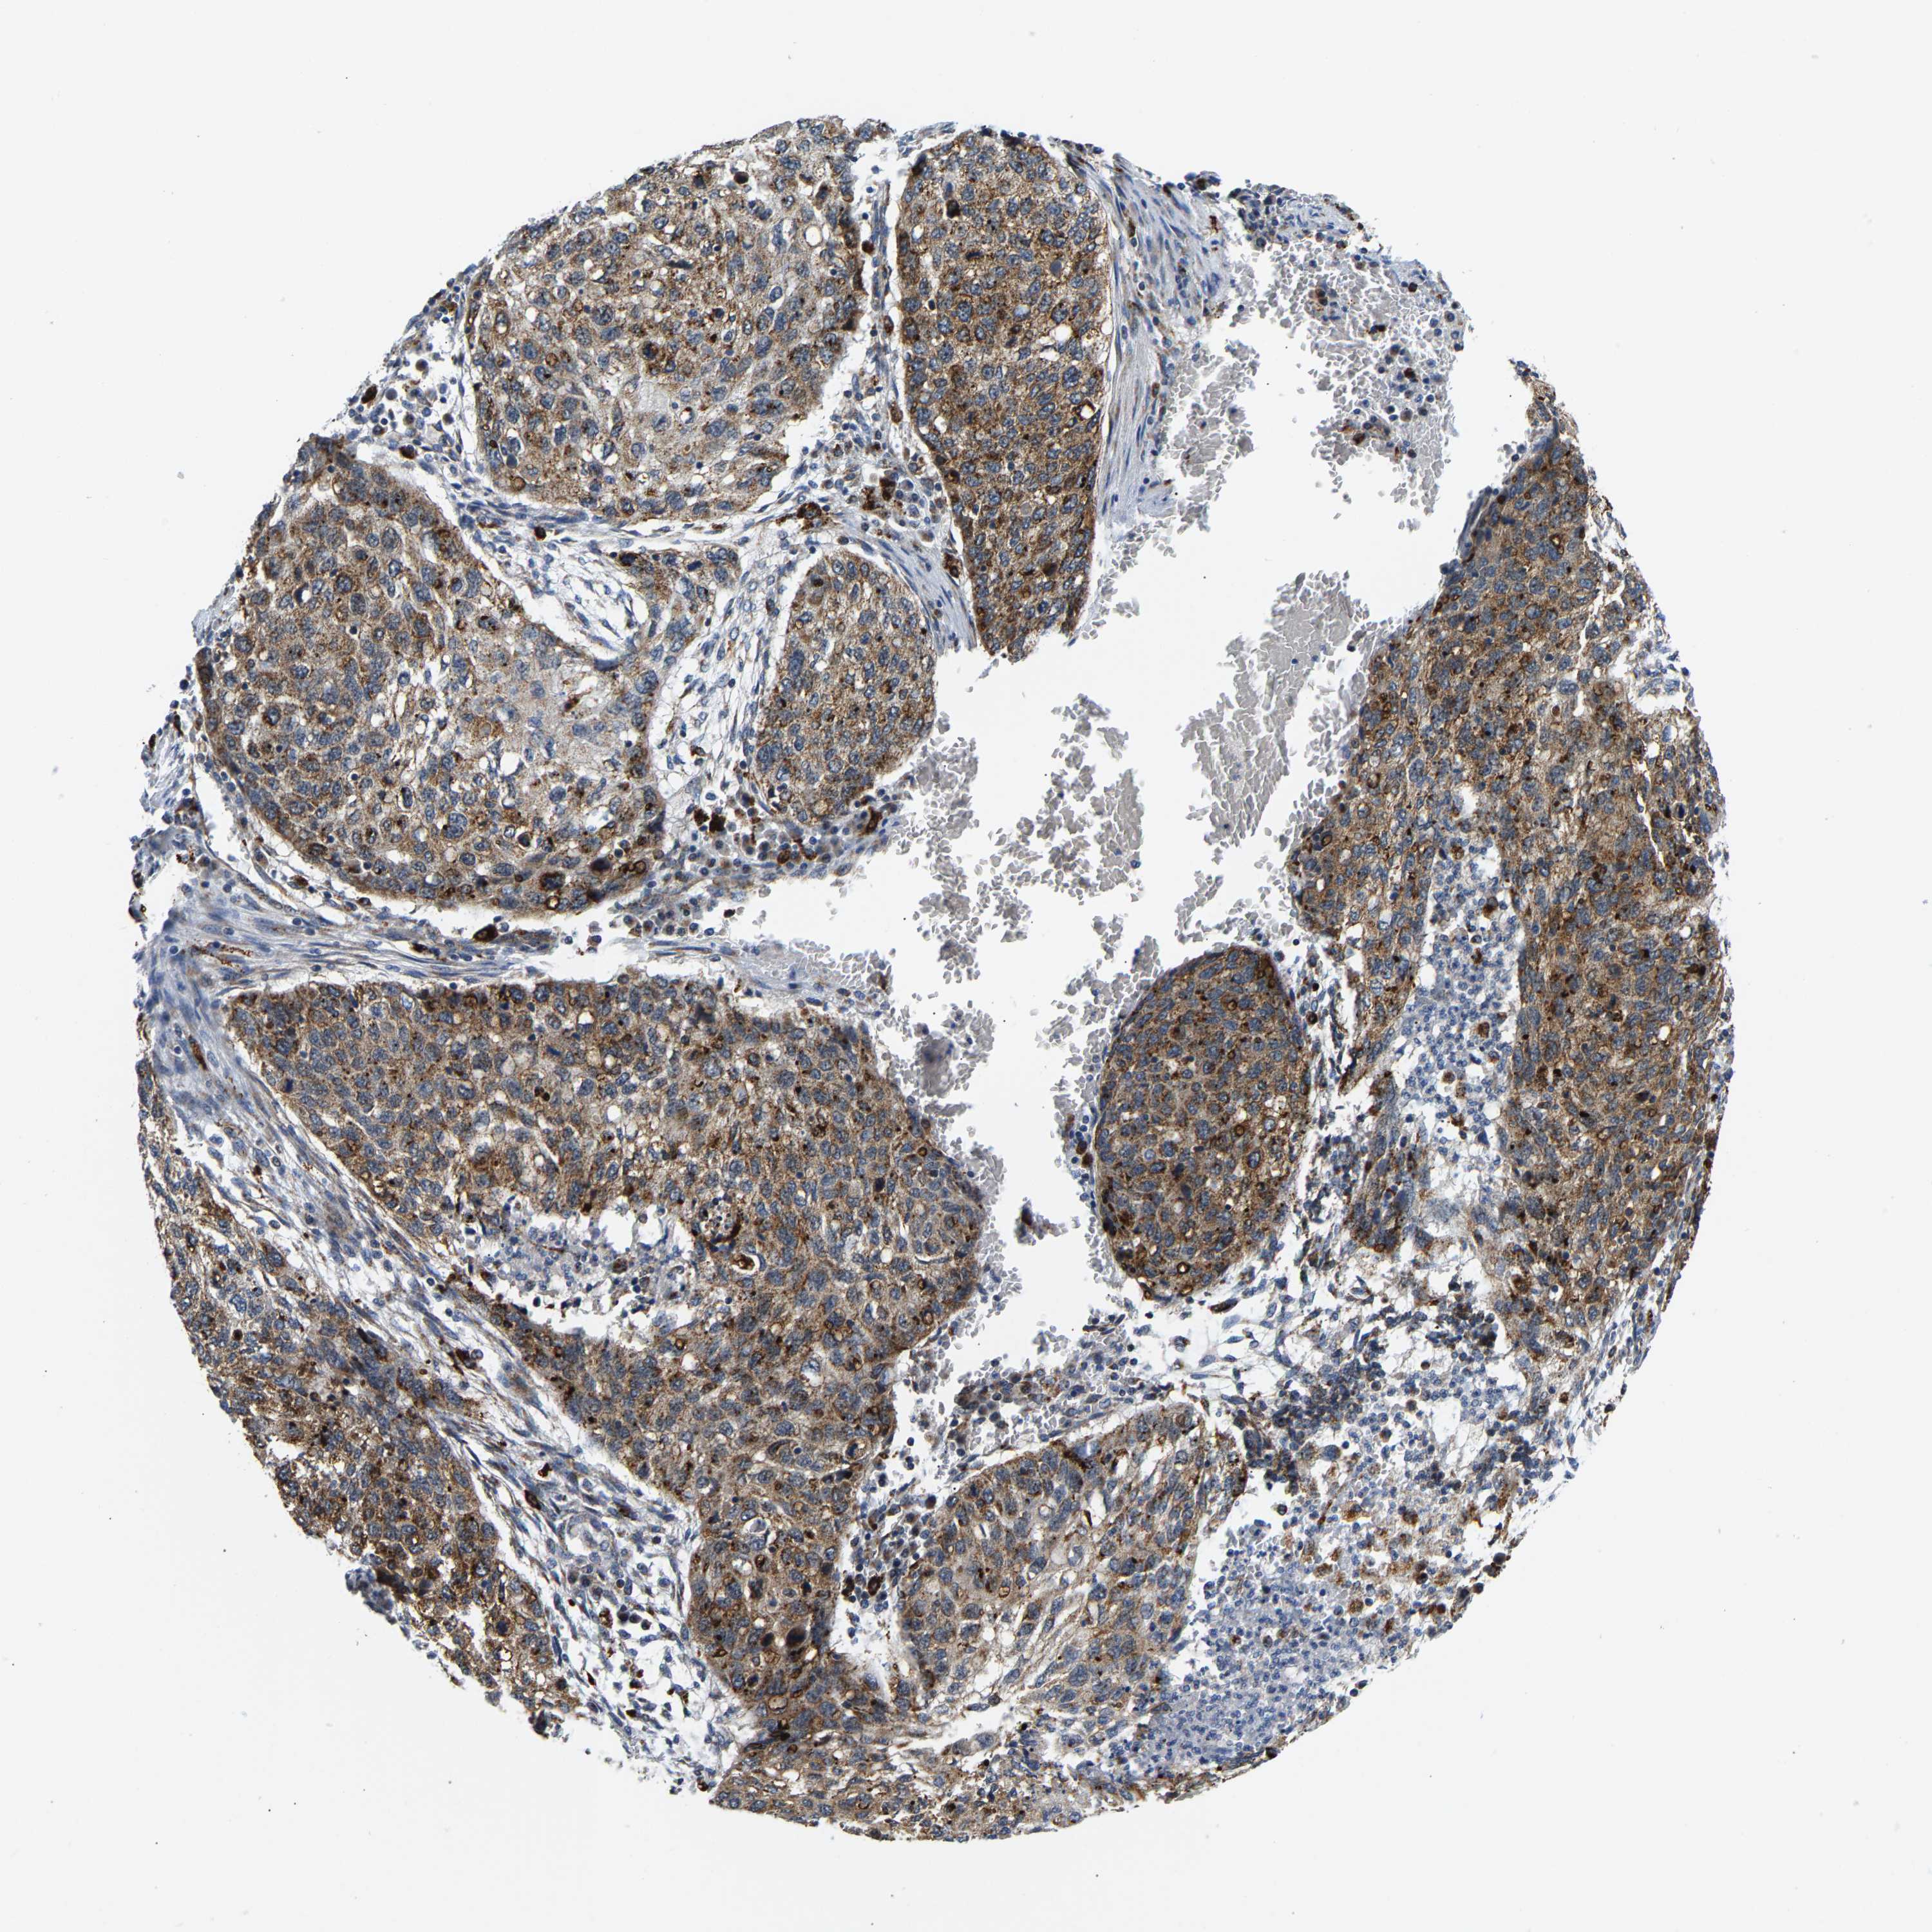

CANCER LUNG CANCER Show tissue menu

GIMAP7 is potential prognostic, high expression is favorable in Lung Adenocarcinoma (TCGA)